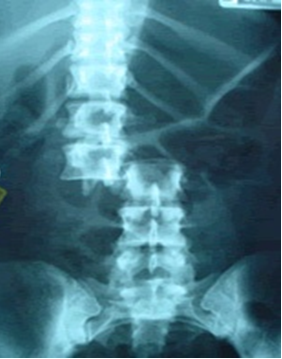

Fracturas de columna vertebral

La incidencia anual de fracturas de columna se estima en 64 de cada 100.000 habitantes por año mientras que la de lesiones medulares asociadas está en torno a 4 de cada 100.000 habitantes. La localización torácica representa el 33% de los casos frente al 46% de la lumbares, siendo las primeras las que mayor índice de lesiones neurológicos presentan (16% frente a un 7%). La mortalidad global asciende a un 4-5%. La población afectada con mayor frecuencia es la de los varones de entre 15 y 25 años; las causas más importantes son: los accidentes de tráfico (40-55%), las caídas desde altura (30-65%) normalmente en horas de trabajo , los accidentes laborales (10-20%) y los traumatismos deportivos (6-13%).